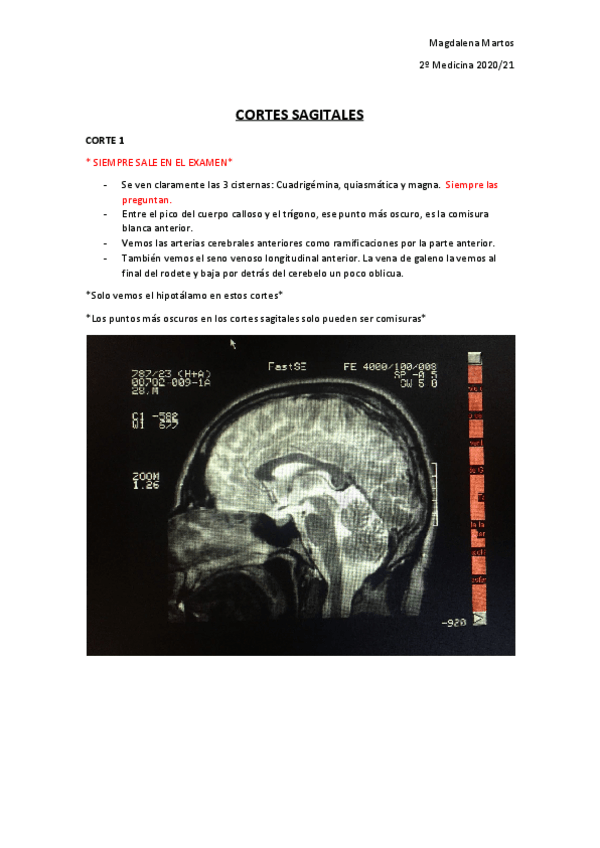

RESONANCIAS EXAMEN PRÁCTICO

He publicado nuevos apuntes de 2º Neurobiología: RESONANCIAS EXAMEN PRÁCTICO

Cortes-Sagitales-Practico-Neuro.pdf